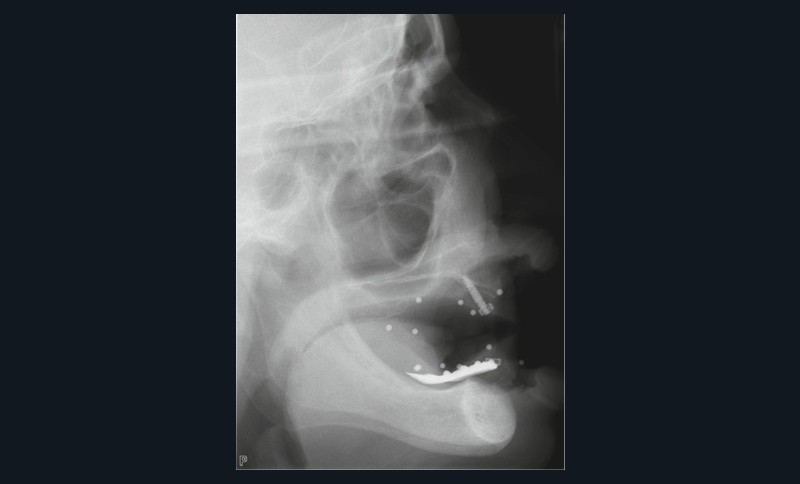

- appui muqueux : sa précision est inférieure. Réservé aux cas d’édentement total, il est conçu à partir d’un alignement avec une prothèse amovible complète comportant des marqueurs radio-opaques (fig. 5 à 8). Le risque d’imprécision est majoré par la dépressibilité de la muqueuse, la tuméfaction des tissus mous due à l’anesthésie, ou le positionnement initial en s’aidant de l’occlusion ;